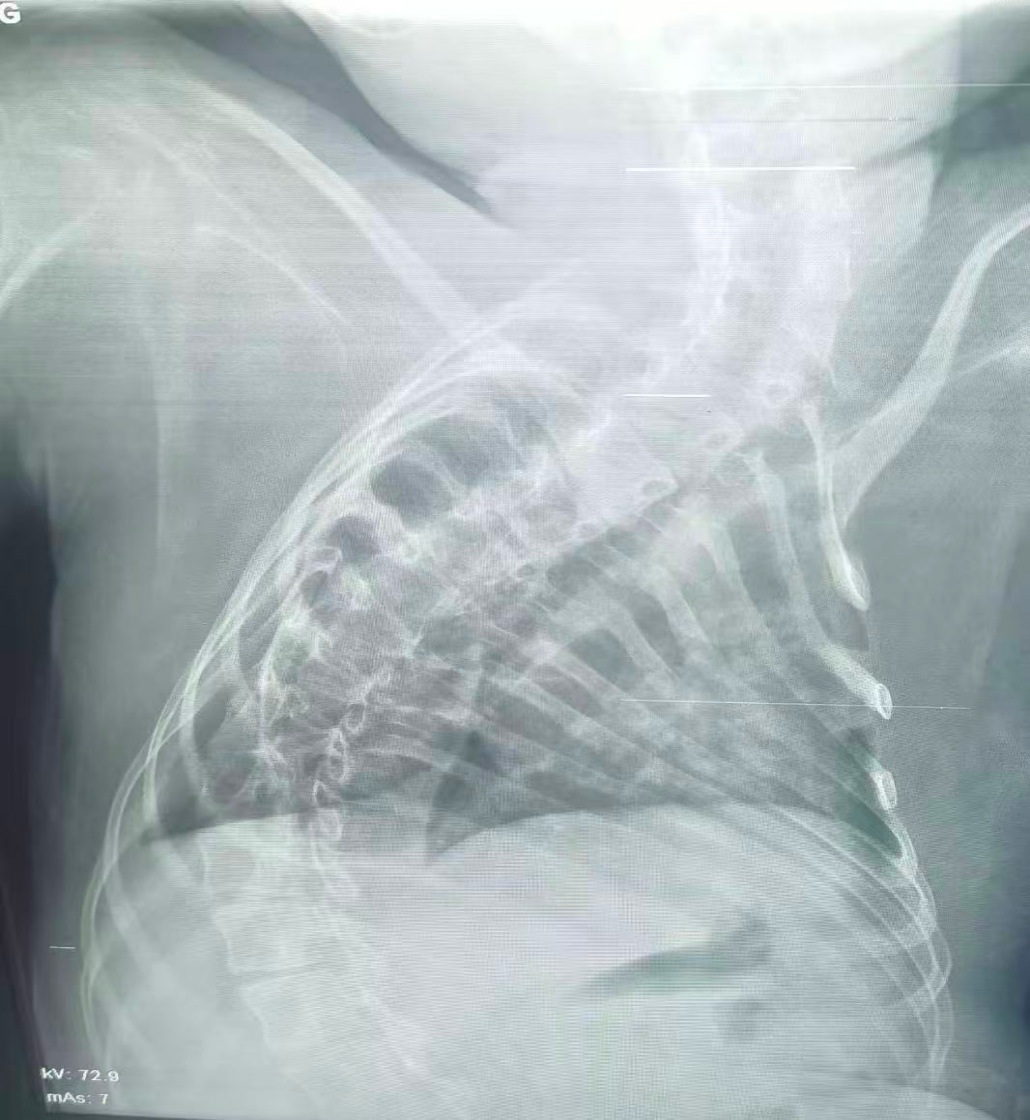

治療前

該患兒因患脊髓性肌萎縮癥長(zhǎng)期臥床,呼吸肌已嚴(yán)重?zé)o力,自主呼吸微弱且?guī)缀鯁适Э人耘盘的芰?,此次并發(fā)支氣管肺炎后,肺部感染迅速加重,生命已然懸于一線。更棘手的是,嚴(yán)重的脊柱側(cè)彎使患兒胸廓畸形、氣道解剖結(jié)構(gòu)明顯移位,常規(guī)纖支鏡進(jìn)鏡路徑完全失效,扭曲狹窄的氣道如同縱橫交錯(cuò)的“迷宮”,每一步操作都必須精準(zhǔn)到毫米級(jí)別。